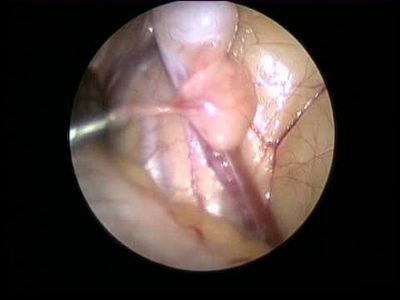

Лапароскопия – лапароскоп; труба с крошечной видеокамерой, приложенной до конца, вставляется через маленький разрез в брюшной полости пациента. Не произошедшее яичко может быть исправлено хирургически во время этой процедуры.Открытой хирургии – в редких осложненных случаях хирург, вероятно, придется исследовать непосредственно в брюшной полости через больший разрез.Если оба яичка не произошлись, доктор может хотеть проверить пол ребенка.

Замочная скважина (лапароскопическая) хирургия обычно используется эти дни для orchidopexies. Хирург делает маленький разрез в брюшной полости мальчика и затем передает маленькие хирургические инструменты через нее.

Яичко перемещено паховый канал вниз и помещено в мошонку с помощью второго разреза. Как правило, паховый канал изолирован, чтобы мешать яичку возвратиться. В большинстве случаев пациент будет в состоянии возвратиться домой в тот же день как хирургия.